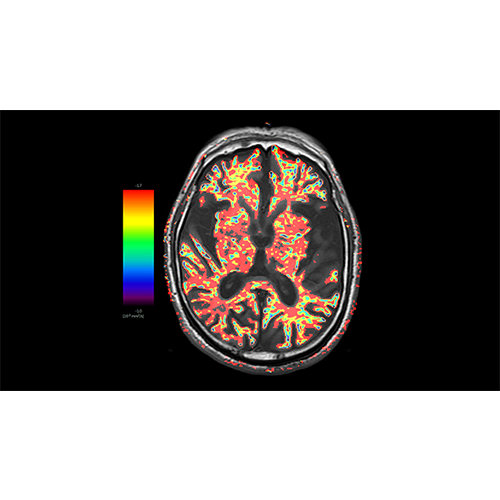

Diffusor Tension Imaging (DTI) module to analyze diffusion-weighted MRI data including calculation of FA maps, fiber tracking and FA group comparisons.

Parametric and non-parametric statistical maps may be superimposed both on the original functional scans as well as onto T1-weighted 2D or 3D anatomical reference scans. Time courses of selected regions-of-interest (ROIs) are available both in 2D and 3D representations. Statistical maps may be computed either in the 2D or 3D representation since structural as well as functional 4D data (space x time) are transformed into Talairach space. This allows you to compare activated brain regions across different experiments and across different subjects

Segmentation of tissue (e.g., isolating the brain, differentiating gray and white matter) is performed using region-growing methods, filter operations as well as the application of 3D templates. Using the mouse it is very easy to explore a 3D volume with superimposed pseudocolor-coded statistical maps in a four-window representation showing a sagittal, coronal, transversal and oblique section. Based on a (segmented) 3D data set a three-dimensional reconstruction of the subjects' head and brain can be calculated and displayed from any specified viewpoint using volume or surface rendering.